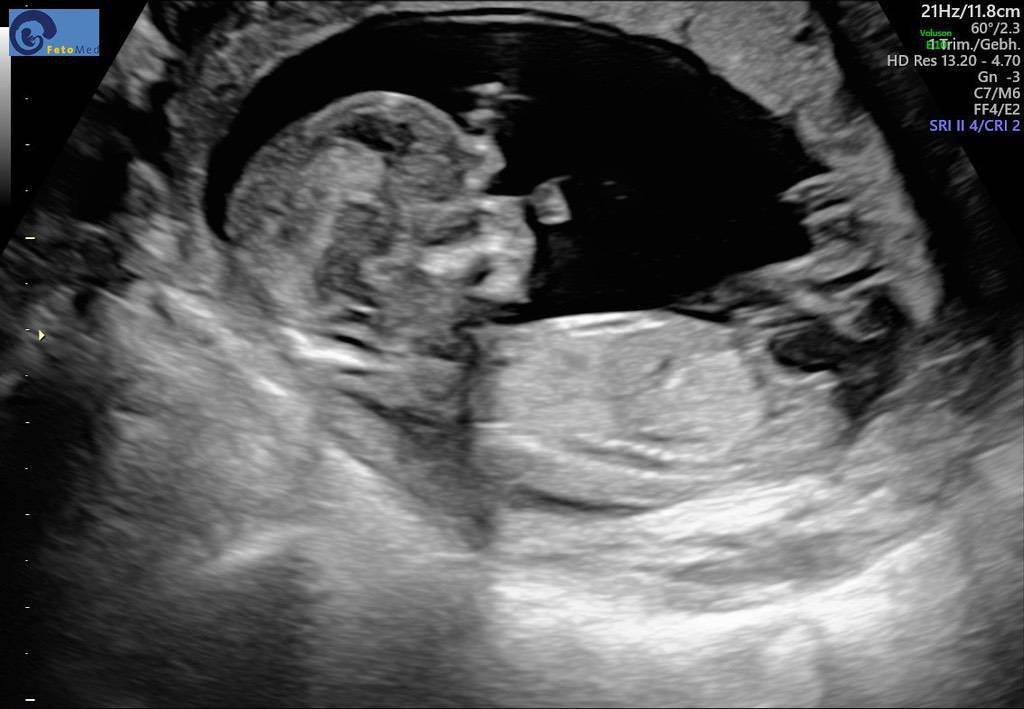

Bei uns hieß es in der 18 woche noch es ist ein Mädchen 😅 heute 23 woche haben wir die Bestätigung bekommen das es doch ein Junge ist mein Arzt hat echt gute Geräte aber in der 18 woche lag es so blöd das man nix richtig sehen konnte ^^ also auch ein Bub versteckt sich gerne mal 😂